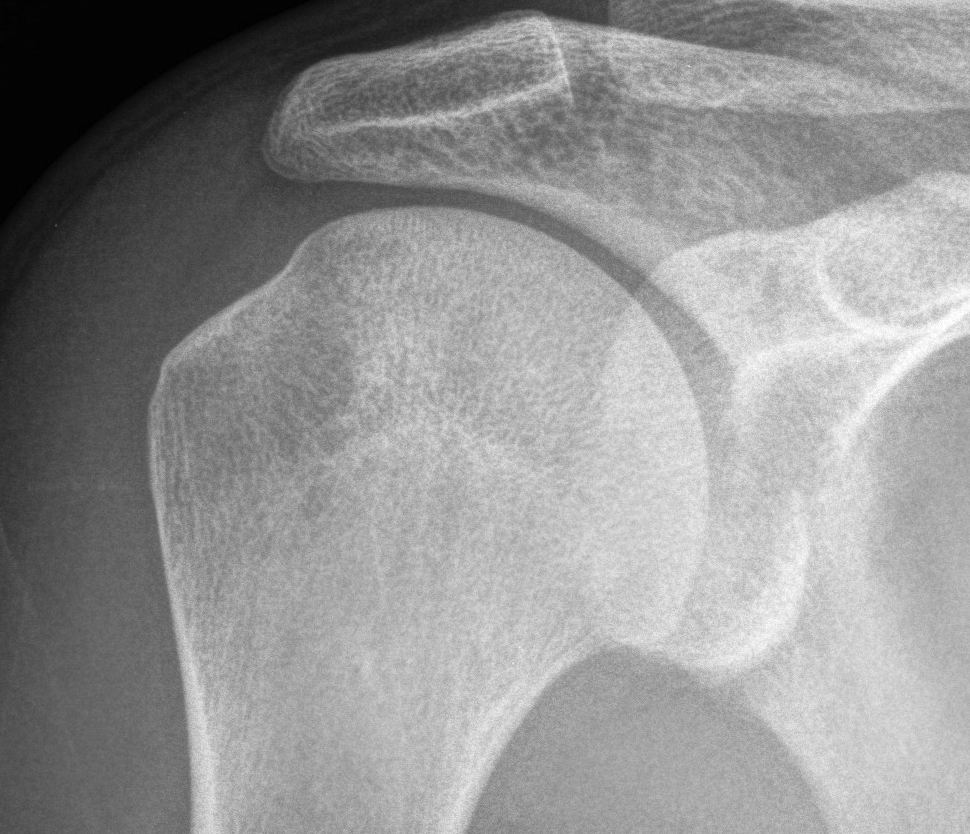

Xray

Bony bankart

Hill Sachs